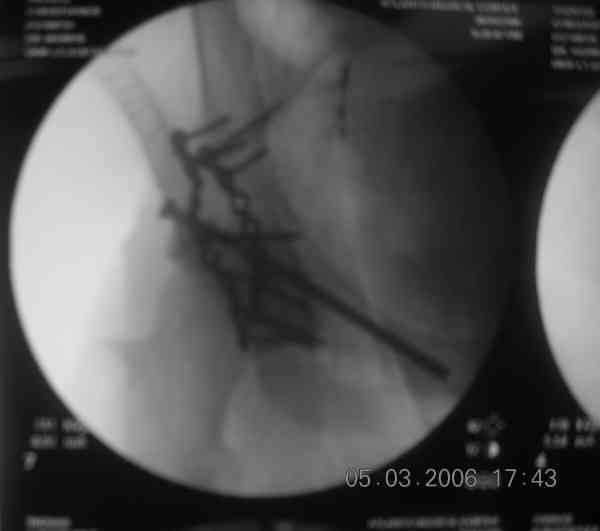

I'll include a few images of a similar injury in a similarly large male patient. This patient "showed up" in our ER c/o hip pain 2 months after being treated in the lateral position, without a quality reduction, without an anterior column transverse supporting implant, with an unbalanced plate applied too medially, with insufficient caudal segment fixation...it took over 8 hours and a 3+ l blood loss to debride the callus from front then

back, excise the HO, release his sciatic nerve, reduce the head-transverse-wall, and fix it...and now it's a staging procedure.

The 2nd example is of a motorcyclist with a transverse fracture-dislocation...he had a closed attempted reduction and placed in traction but the manipulative reduction was not concentric (not unusual for this injury pattern)...so the traction was adjusted to be just enough to disengage the head from the fracture (12#) until he could be cleared for surgery one day after injury...he was treated "urgently" then with a prone KL, clean the fracture, reduce and clamp it, screw it, support with a balanced plate, close, and enjoy...2-3hours, 400cc EBL, blah, blah, blah..